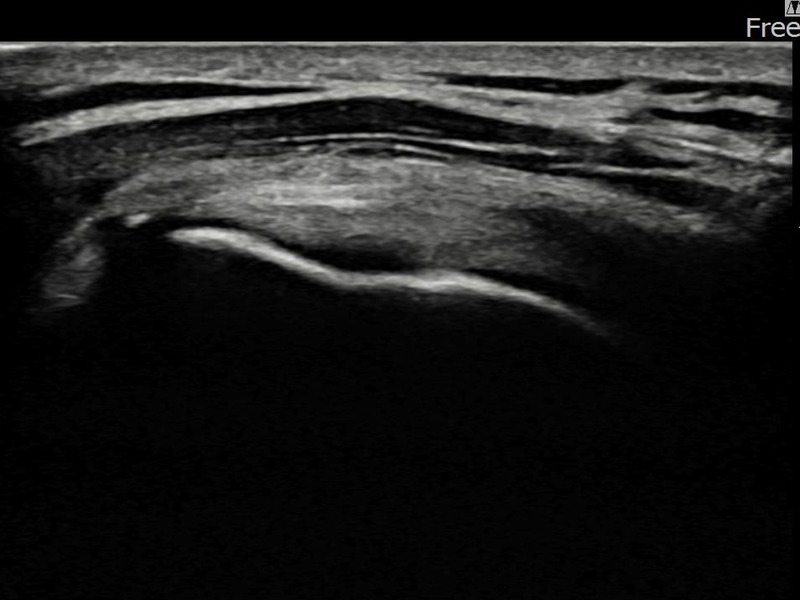

김ㅇㅇ님 · 좌측 극상근건 점액낭면측 부분파열

좌측 어깨 광범위 파열로 팔 들어올리기가 매우 어려웠습니다. 축소봉합술 시행 후 점액낭면측 힘줄 구조가 안정화되었습니다.